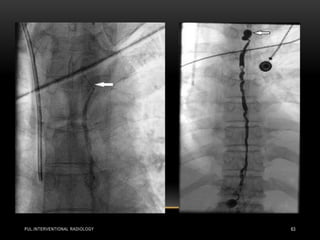

• Pulmonary angiography in a 57-year-old woman in shock from

acute bilateral massive PE. Initial right (a) and left

(b) pulmonary angiograms show near-complete obstruction.

Pulmonary artery pressure was 73/18 mm Hg. Final right (c) and

left

(d) images after suction thrombectomy and catheter-directed

thrombolytic agent injection into each main descending

pulmonary

artery. Pulmonary artery pressure was reduced to 36/16 mm Hg.

(Images courtesy of Daniel Y. Sze.)